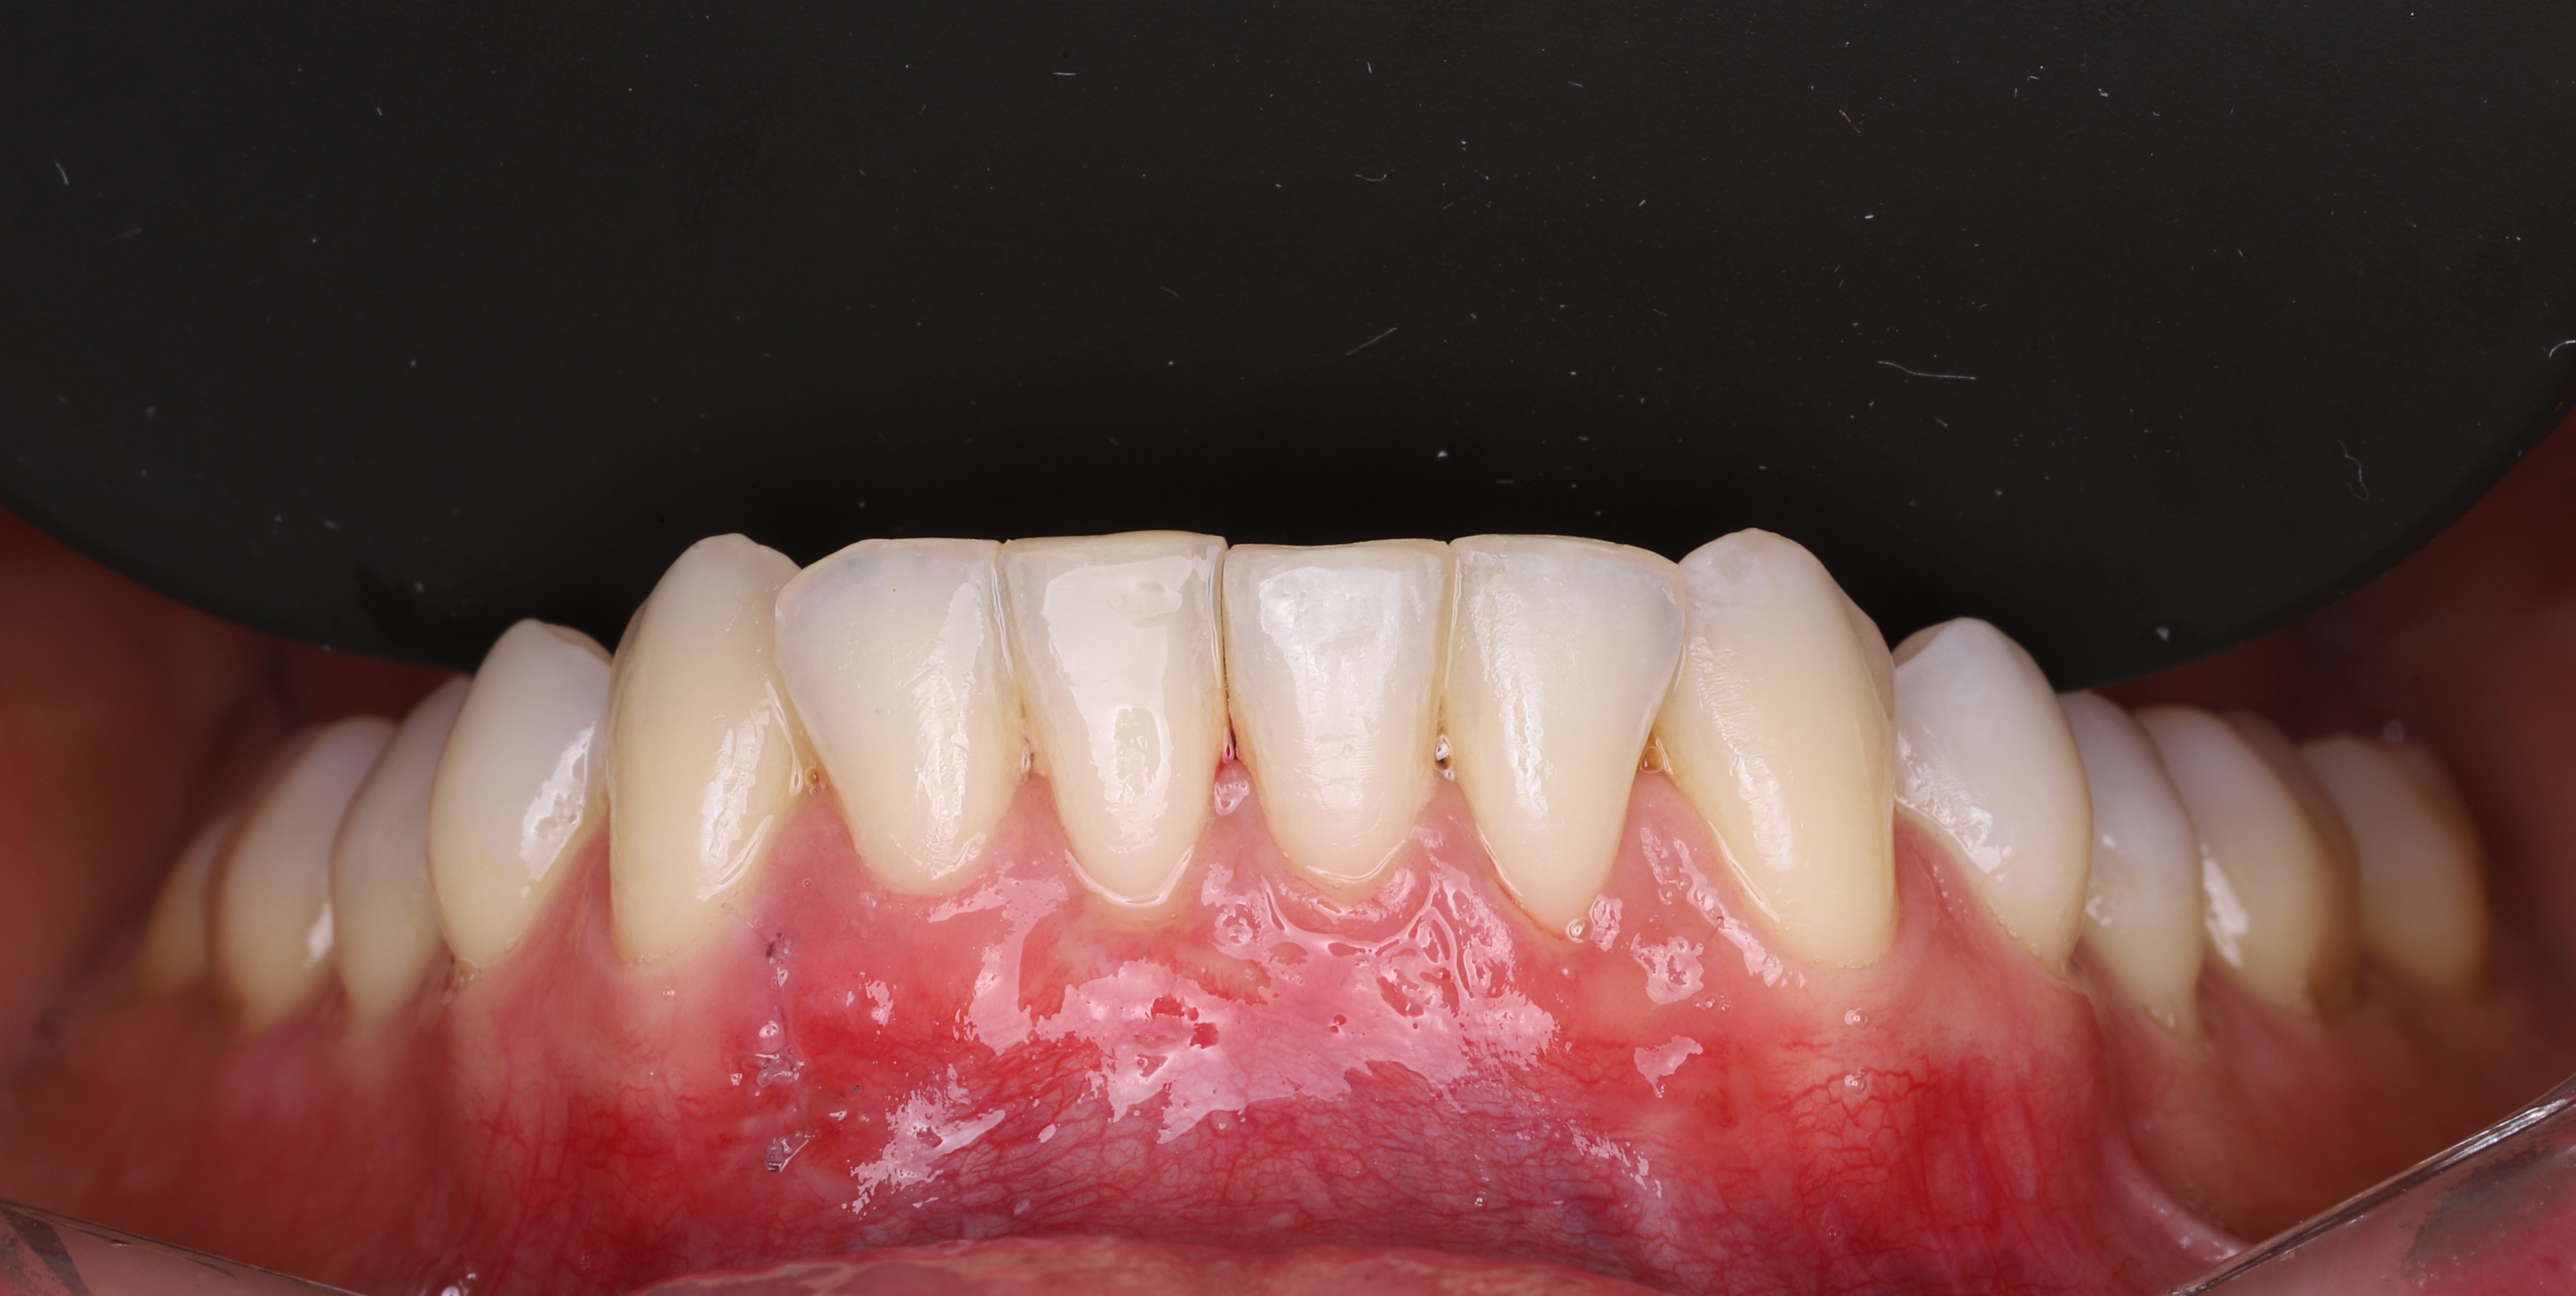

• Complete coverage of the exposed root and restoration of a harmonious gum line.

• Reduction of tooth sensitivity and prevention of root caries.

• Thickening and strengthening of the gingival margin for long-term stability.

• Noticeable improvement in smile aesthetics, especially in the anterior region.